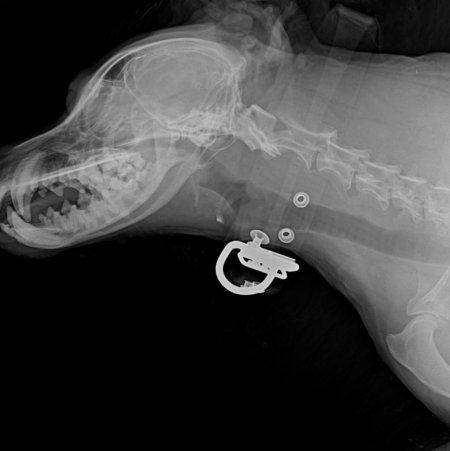

Охранники связались с Ольгой, которая занимается помощью животным, и раненую собаку отвезли в ветклинику. Визуальный осмотр и рентген показали множественные травмы челюсти, разрывы пасти, выбитые зубы. Если бы пес вцепился не в пасть, а в позвоночник, исход, вероятно, был бы смертельным.